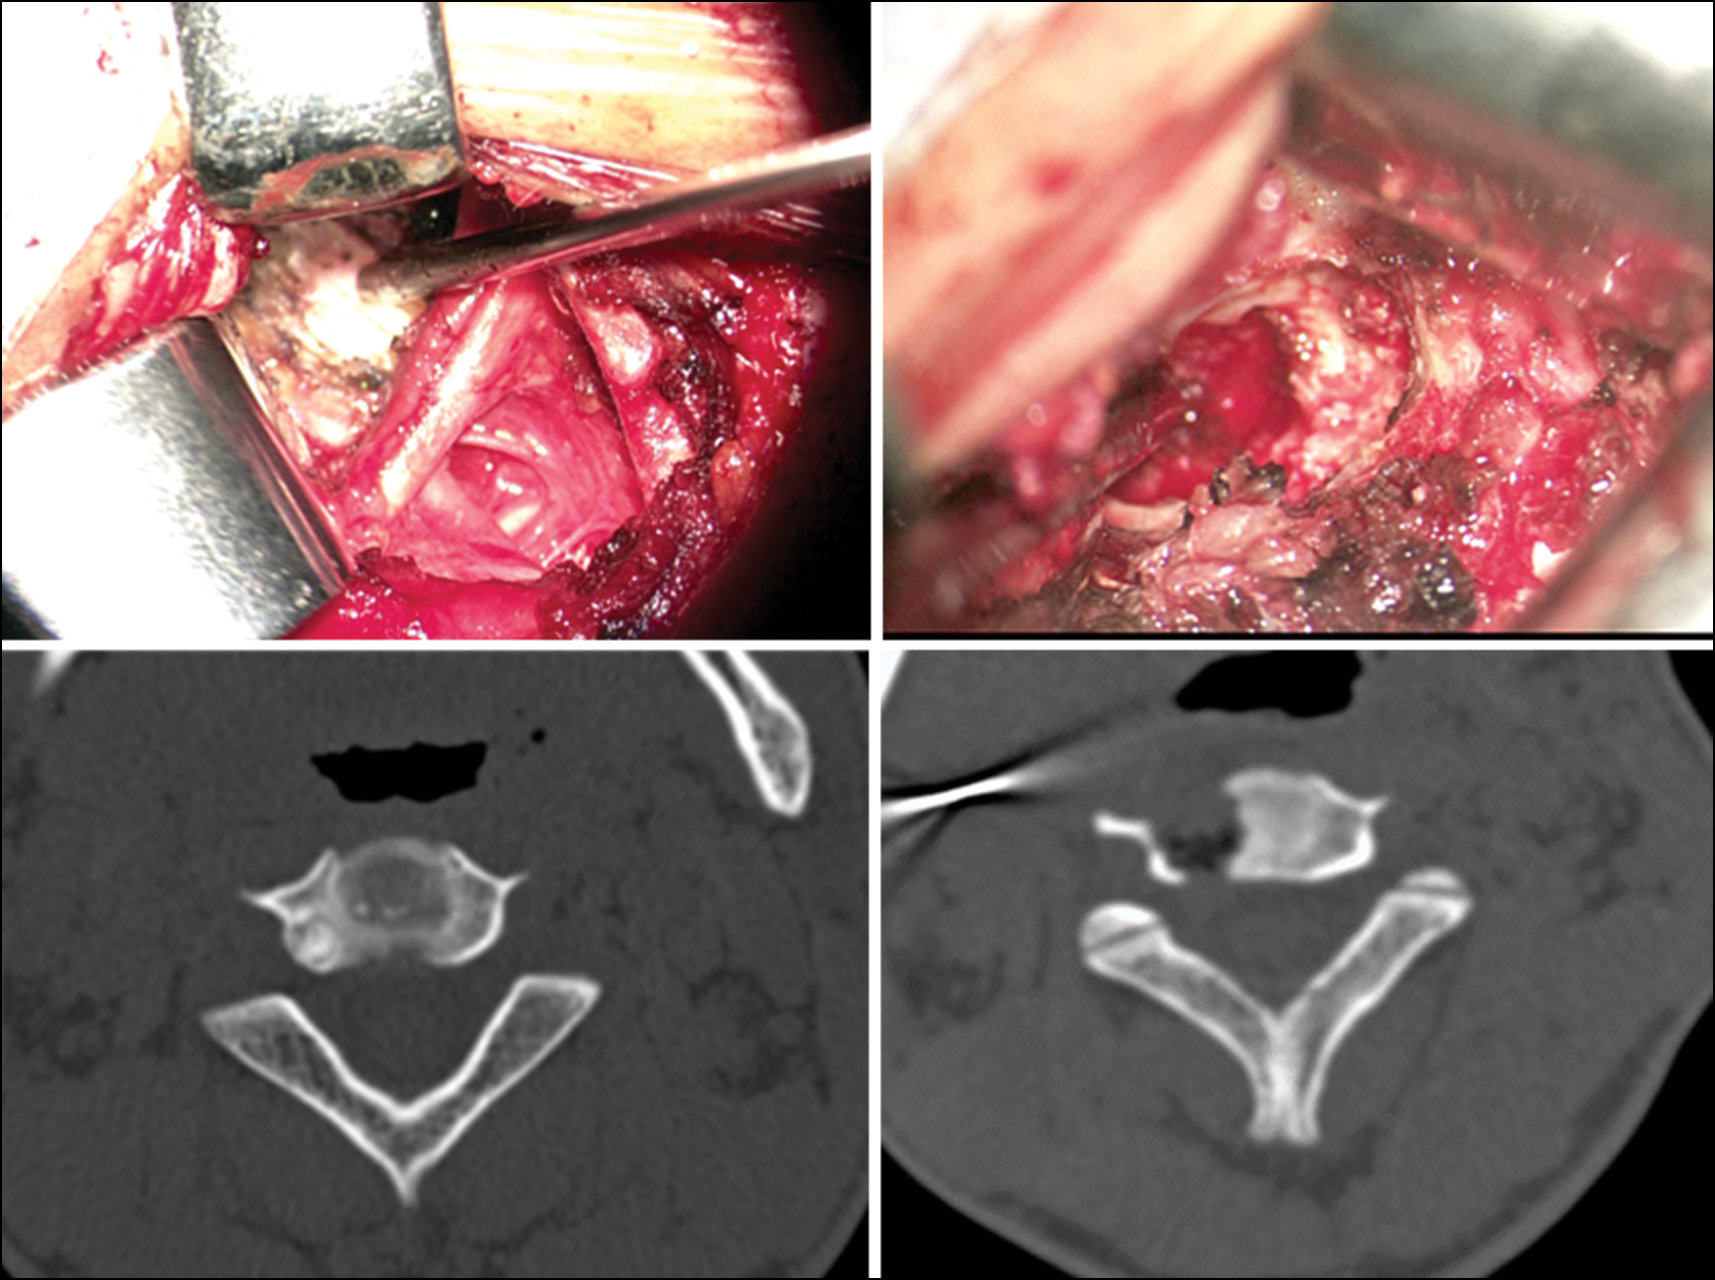

Выбор техники выполнения удаления основывался на уровне поражения и локализации опухоли: в передней, средней или задней опорной колонне. Как было отмечено, при проведении РЧА и ЛТА опухоли присутствует высокий риск термического повреждения в случае её расположения вблизи магистральных сосудов и нервных окончаний [6, 7, 12]. В связи с этим в данном случае предпочтение отдавалось открытому методу резекции. При безопасной локализации опухоли (более 5 мм от магистральных сосудов и невральных структур) целесообразно проведение РЧА и ЛТА очага (рис. 1).

Рис. 1. Радиочастотная абляция остеоид-остеомы дужки позвонка под КТ-навигацией.

Fig. 1. Computed tomography-guided radiofrequency ablation of a vertebral arch osteoid osteoma

В нашей выборке было проведено 6 вмешательств с применением лазерной деструкции и РЧА. Во всех случаях стойкое купирование болевого синдрома достигалось уже на третьи сутки после проведённой манипуляции.